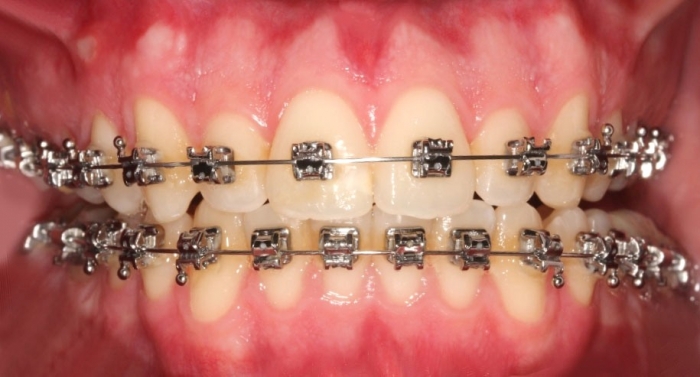

Mordida inicial - Clínica Cliniface

Mordida inicial